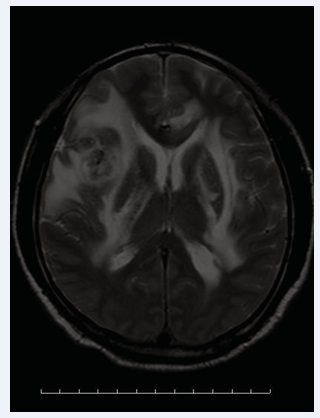

Further craniotomy was planned. However, treponema pallidum antibody (TPPA)25.75S/OO, positive. Serum RPR was 1:8. Furtherlumbar puncture, cerebrospinal fluid pressure of 230mmH2O and cerebrospinal fluid RPR of 1:2. Afterwards,benzathine penicillin G, 2.4 mIU,once a week for three times,was administrated. The above symptoms of the patient were significantly remission, the left extremities no longer paralyse, and could walk in the ward. Three months later, the reexamination of the head MRI enhancement suggested multiple abnormal signals in the right basal node/radiographic crown, which was significantly reduced than before (Figure 2).

Figure 2 Occupying lesion fade away (arrow).

Figure 2: Occupying lesion fade away (arrow).

The patient was eventually exempted from surgery and was diagnosed with neurosyphilis.